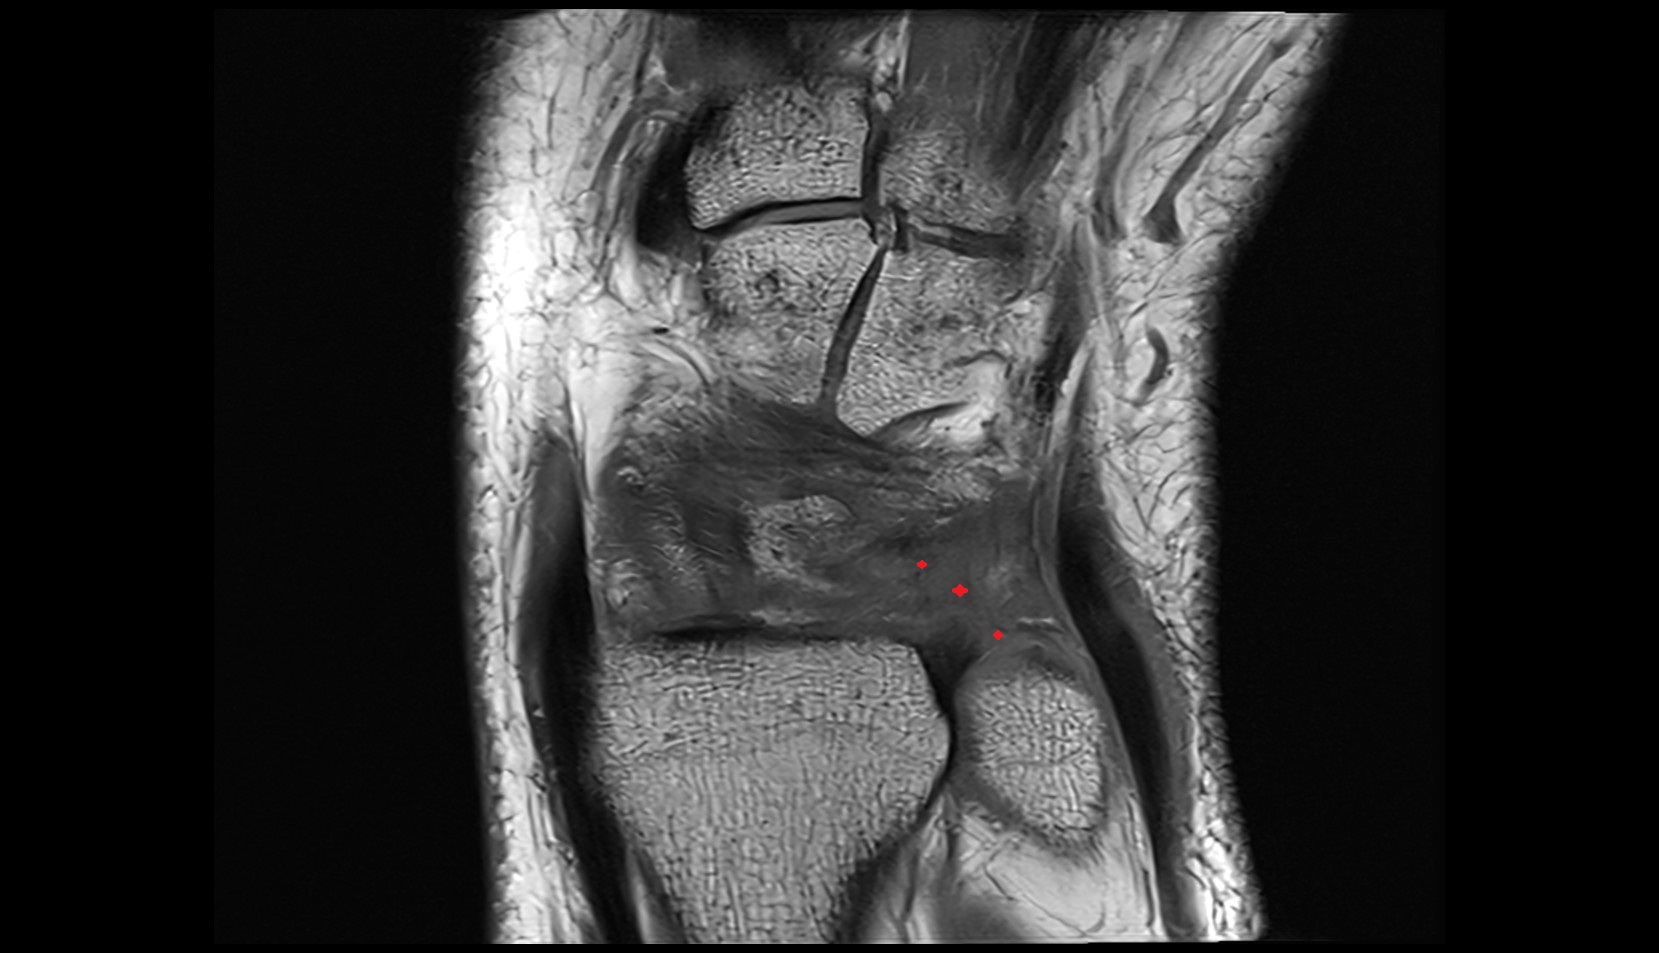

- Medial meniscus

- Lateral meniscus

- Anterior horn of medial meniscus

- Posterior horn of medial meniscus

- Body of medial meniscus

- Anterior root of medial meniscus

- Posterior root of medial meniscus

- Anterior horn of lateral meniscus

- Posterior horn of lateral meniscus

- Body of lateral meniscus

- Anterior root of lateral meniscus

- Posterior root of lateral meniscus